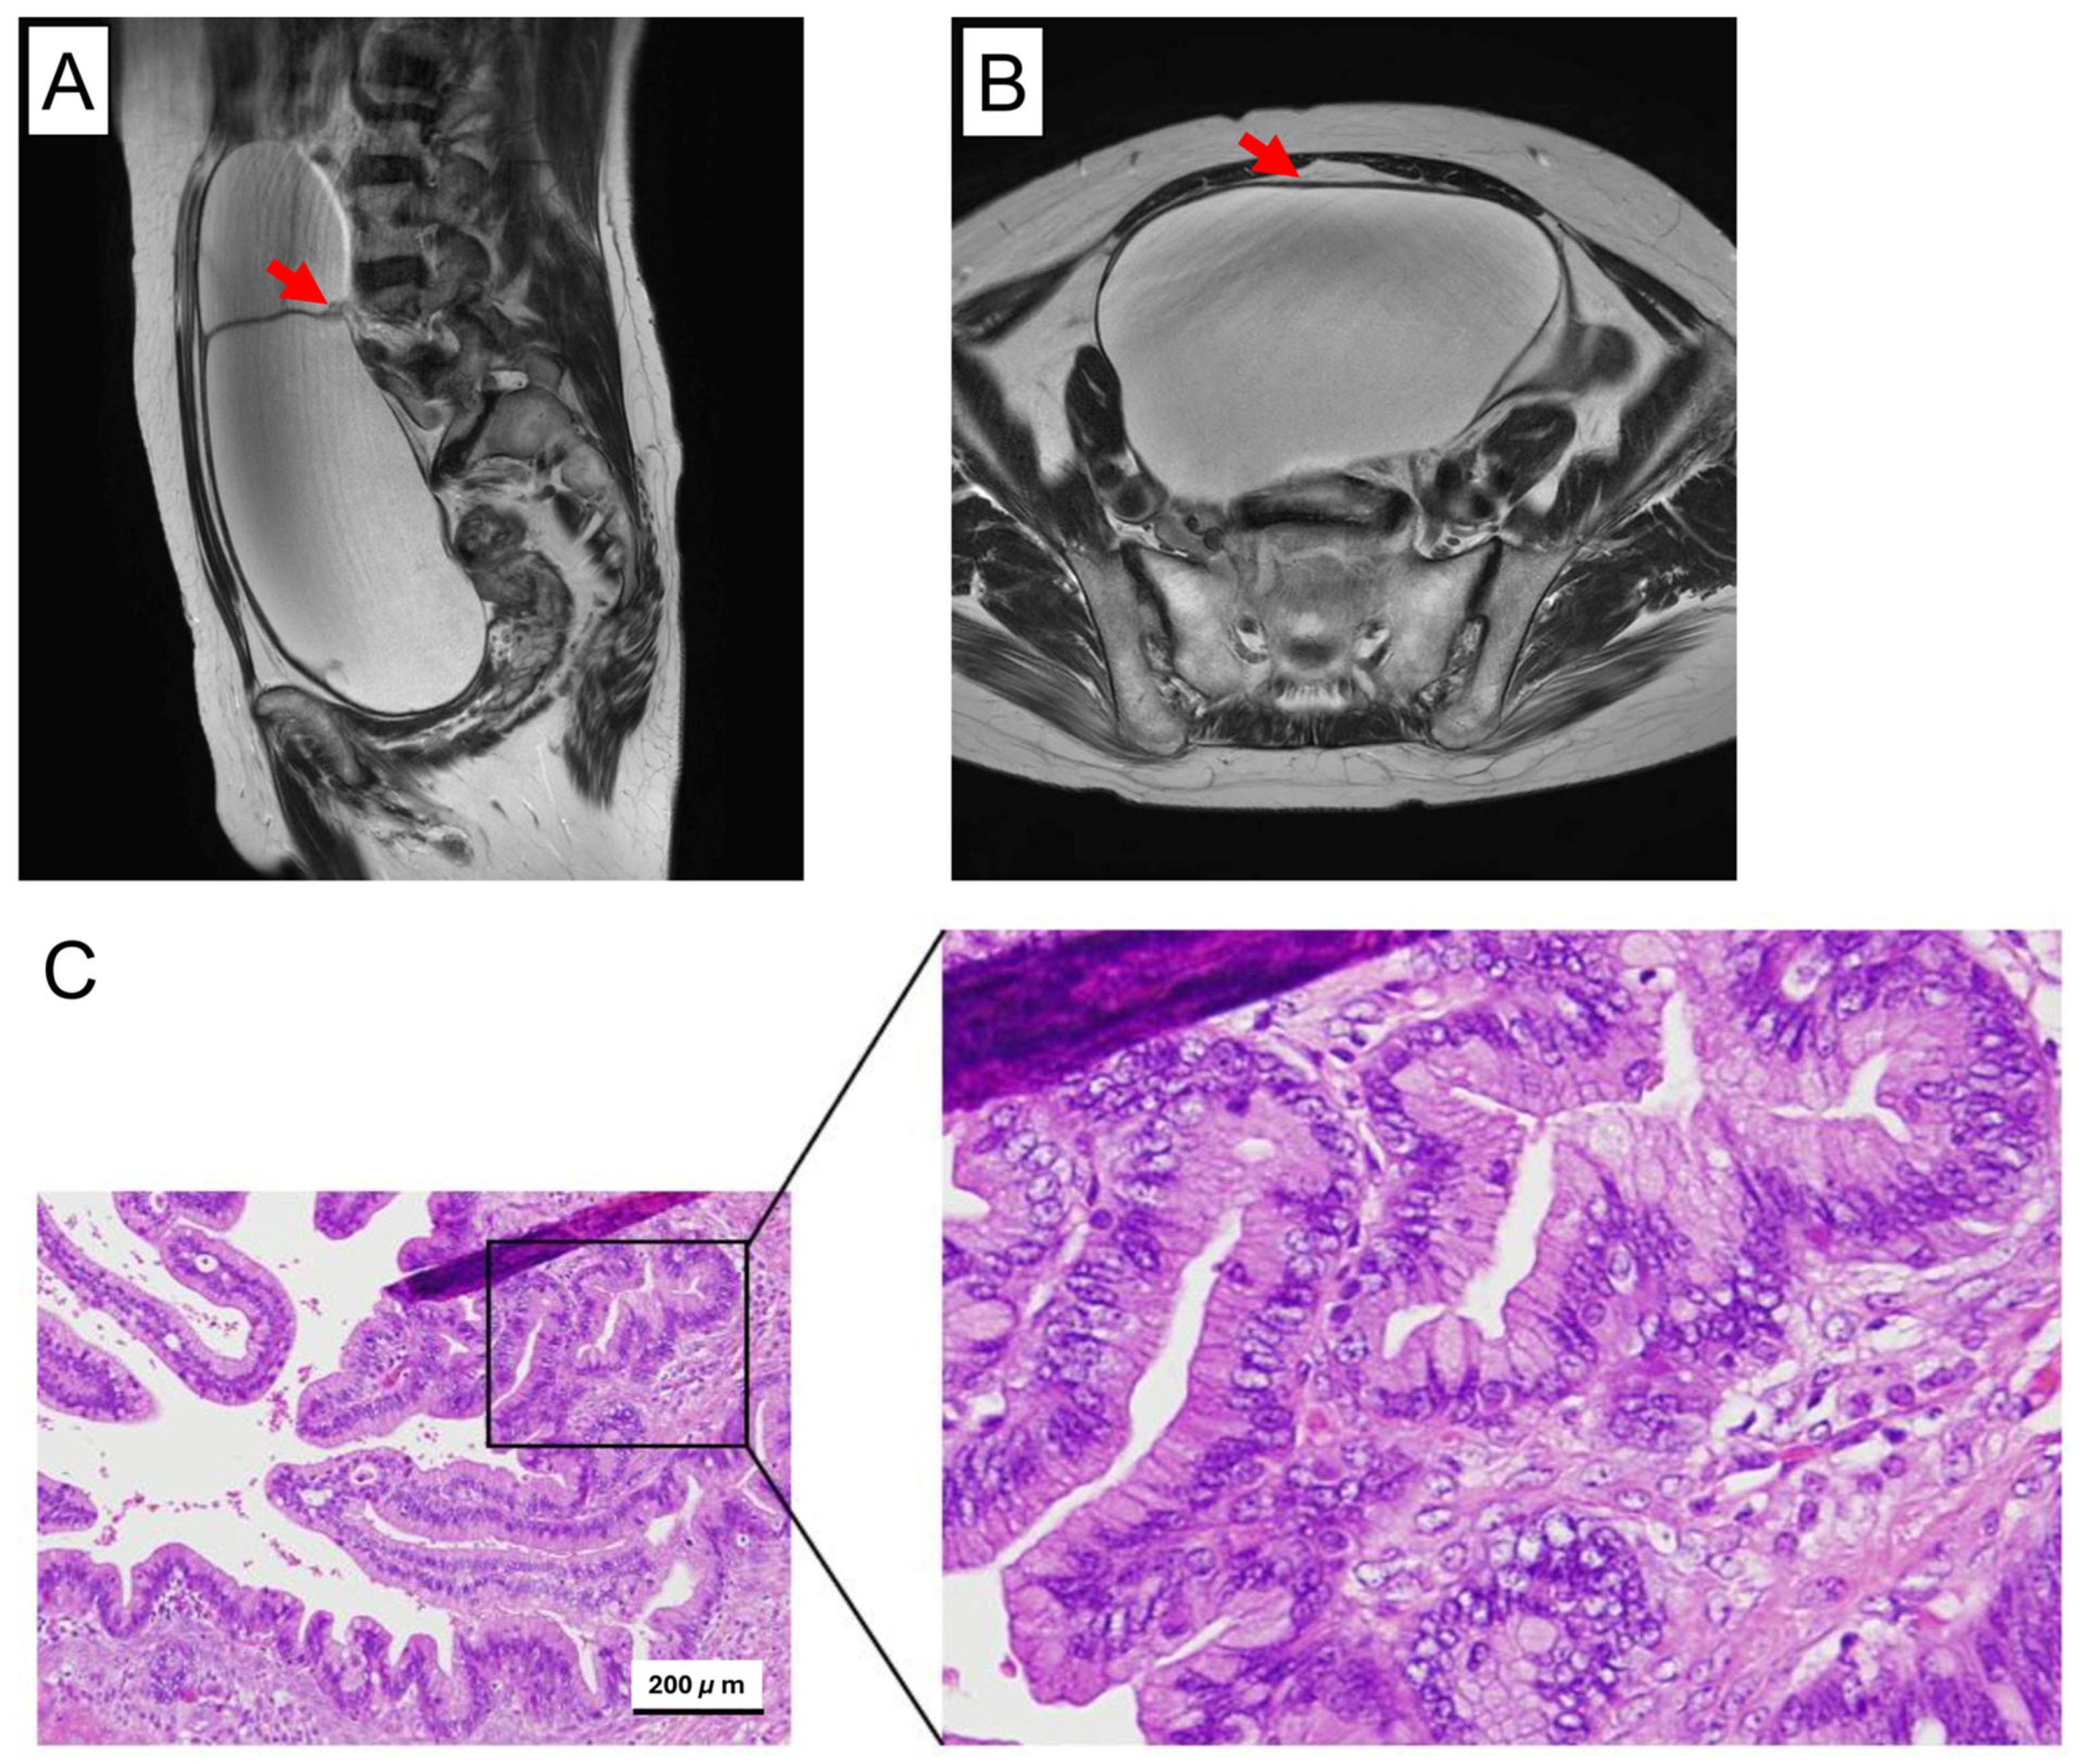

3.1. Histopathological Overview of the Original Tumor

3.2. Establishment of the MBOT Cell Lines